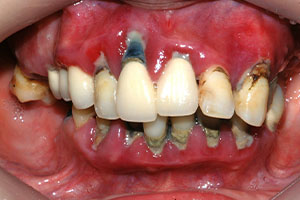

치료증례 전후사진

Before & After